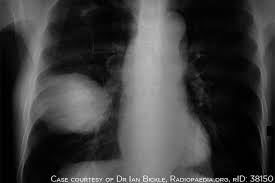

Decreased function of the body immune system. Lung carcinomas derive from transformed, malignant cells that originate as epithelial cells, or from tissues composed of epithelial cells. Most people who develop lung cancer have a history of smoking. Like all cancers, lung cancer begins at the cellular level and is the result of abnormal cells that reproduce rapidly and out of control. Only 16% of lung cancers are identified at an early stage, making treatment and survival much more difficult. Overall, the most common sites of lung cancer metastases incude: Tell your doctor or specialist nurse if you're worried about a symptom or if it continues for more than a few days. Carcinoid tumors are also sometimes categorized by where they start in the lung: Fluid builds up in the lungs. A pancoast tumor is a type of lung cancer that grows in the upper part of your lung and spreads to your ribs, vertebrae in your spine, nerves, and blood vessels. Having problems breathing can be scary, but the good news is there are practical tips to prevent, manage and treat this common complication of lung cancer. The cancer cells are between 3 cm and 4 cm and may be moving into other areas of the lung such as the main airway or membrane. Central carcinoids form in the bronchi, which are the large airways located near the center of the lungs.

These stages come from the tnm staging system. Lung cancer's obvious symptom is shortness of breath. Cancers also may be described by the type of cell that formed them, such as an epithelial cell or a squamous cell. Fluid builds up in the lungs. Worsening — or return — of bronchitis. For example, lung cancer starts in the lung, and brain cancer starts in the brain. It can start in one area of the body (in this case, the lungs) and spread (or metastasize) to other organs or the bones. Each year, hundreds of thousands of americans are diagnosed with lung cancer.tragically, lung cancer is amongst the deadliest form of cancer, claiming more lives each year than breast, prostate, and colon cancers combined.with other forms of cancer being extremely treatable, many are. How do we know particle pollution causes lung cancer? Lung cancer lung cancer is a type of cancer that begins in the lungs. Cancer tumors are fragile and often bleed causing the person to cough up blood. Having problems breathing can be scary, but the good news is there are practical tips to prevent, manage and treat this common complication of lung cancer. Because of where these tumors grow,.